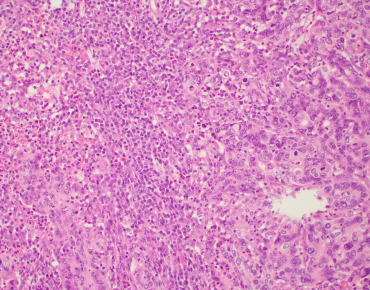

Over the past few years, Roberto Salgado, Sherene Loi and Carsten Denkert have developed the International Immuno-Oncology Biomarker Working Group on Breast Cancer, with members including expert clinical research groups, pathologists, clinicians and statisticians worldwide currently knowledgeable in the field of Immune-oncology Biomarkers. The purpose of this Working Group is to develop, in a timely manner, standards on the assessment of Immuno-Oncology Biomarkers to aid pathologists, clinicians and researchers in their research and daily practice.

The group has worldwide representatives of known clinical research groups from high level expert centers across all continents (US, EU, the Middle East and Japan) like the MD Andersen Cancer Center (US), Weill Cornell University (US and Qatar), Memorial Sloan Kettering Cancer Center (US), Dana Farber Cancer Institute (US), Peter Mac Callum Cancer Center (Aus), Insitut Gustave Roussy (EU), European Institute of Oncology in Milan (EU), Jules Bordet (EU), National Cancer Institute, Lima (South America), etc..

Since the Working Group hosts expert research teams it is the perfect place to establish collaborations between group members. The member list will include the research interest of each group member. Importantly, we don’t expect each member to share publicly the details of their own projects as we respect each group’s confidentiality policies.

This group is an informal pathologist-driven group, so pathologists with interest and expertise to join the mailing-list are welcome.